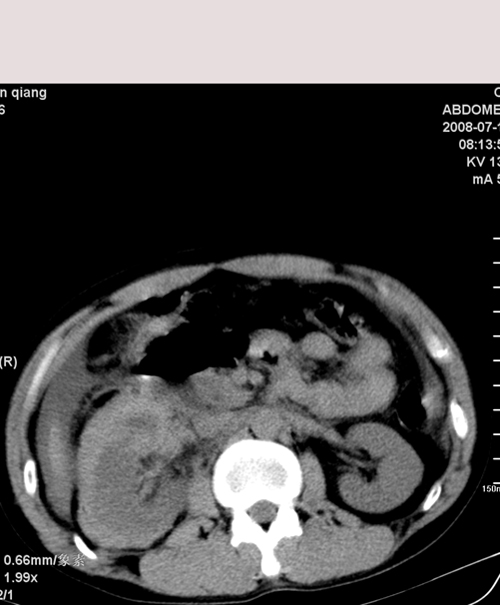

以下是引用muzi888在2008-7-15 10:45:00的发言:[br]大量腹腔积液,气腹,肾皮质弧形高密度影,诊断;1 空腔脏器穿孔 2 右肾包膜下血肿

以下是引用随光逐影在2008-7-15 11:18:00的发言:[br]考虑为:1)腹部空腔脏器穿孔。2)右肾破裂并肾包膜下血肿,肾盂积血。3)腹水(血)。